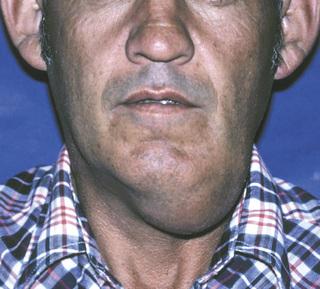

sialadenosis

Enlargement of the parotid and submandibular glands secondary to alcoholism. Sialography demonstrates a “leafless tree” pattern.